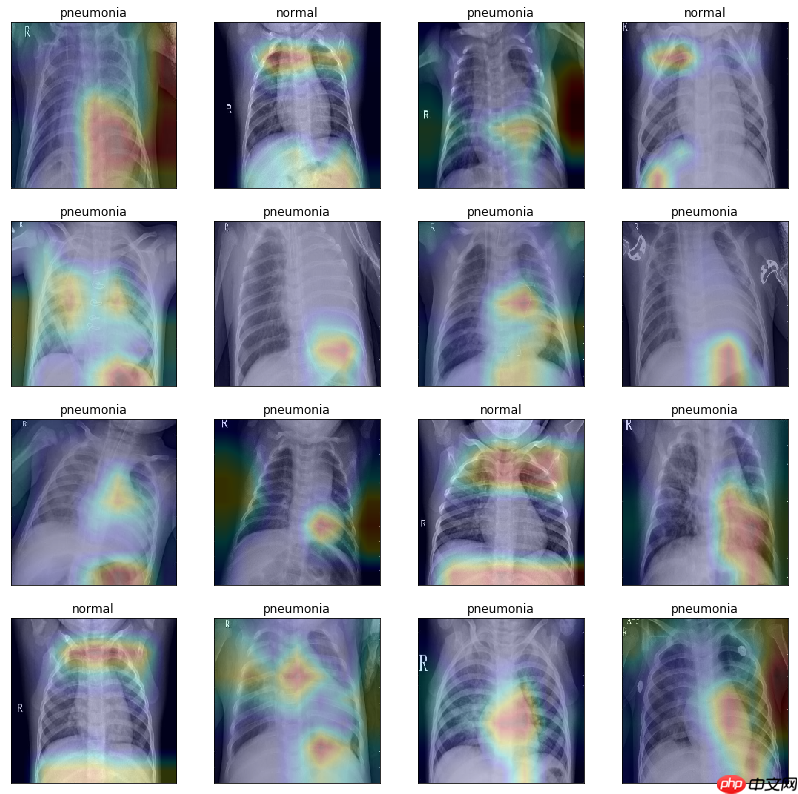

绘制类激活图,可视化模型效果

# 获取 Grad-CAM 类激活热图def get_gradcam(model, data, label, class_dim=2): conv = model.conv_layer(data) # 得到模型最后一个卷积层的特征图 predict = model.last_layer(conv) # 得到前向计算的结果 label = paddle.reshape(label, [-1]) predict_one_hot = paddle.nn.functional.one_hot(label, class_dim) * predict # 将模型输出转化为one-hot向量 score = paddle.mean(predict_one_hot) # 得到预测结果中概率最高的那个分类的值 score.backward() # 反向传播计算梯度 grad_map = conv.grad # 得到目标类别的loss对最后一个卷积层输出的特征图的梯度 grad = paddle.mean(paddle.to_tensor(grad_map), (2, 3), keepdim=True) # 对特征图的梯度进行GAP(全局平局池化) gradcam = paddle.sum(grad * conv, axis=1) # 将最后一个卷积层输出的特征图乘上从梯度求得权重进行各个通道的加和 gradcam = paddle.maximum(gradcam, paddle.to_tensor(0.)) # 进行ReLU操作,小于0的值设为0 for j in range(gradcam.shape[0]): gradcam[j] = gradcam[j] / paddle.max(gradcam[j]) # 分别归一化至[0, 1] return gradcam# 将 Grad-CAM 叠加在原图片上显示激活热图的效果def show_gradcam(model, data, label, class_dim=2, pic_size=224): gradcams = get_gradcam(model, data, label,class_dim=class_dim) for i in range(data.shape[0]): img = (data[i].numpy() *127.5 +127.5).astype('uint8').transpose([1, 2, 0]) # 归一化至[0,255]区间,形状:[h,w,c] heatmap = cv2.resize(gradcams[i].numpy() * 255., (data.shape[2], data.shape[3])).astype('uint8') # 调整热图尺寸与图片一致、归一化 heatmap = cv2.applyColorMap(heatmap, cv2.COLORMAP_JET) # 将热图转化为“伪彩热图”显示模式 superimposed_img = cv2.addWeighted(heatmap, .2, img, .8, 1.) # 将特图叠加到原图片上 return superimposed_imgmodel_path = 'checkpoint/final.pdparams'model = ResNet( class_dim=2)para_state_dict = paddle.load(model_path)model.set_dict(para_state_dict)model.eval()test_txt = 'work/data/test_list.txt'test_dataset = XChestDateset(test_txt,val_transform, 'test')test_loader = DataLoader(test_dataset, shuffle=True, batch_size=16 )dataiter = iter(test_loader)images, labels = dataiter.next()num = images.shape[0]row = 4fig = plt.figure(figsize=(14,14))for idx in range(num): ax = fig.add_subplot(row,int(num/row), idx+1, xticks=[], yticks=[]) image = paddle.unsqueeze(images[idx], axis=0) heat_map = show_gradcam(model, image, labels[idx], class_dim=2) heat_map = cv2.cvtColor(heat_map, cv2.COLOR_BGR2RGB) plt.imshow(heat_map) if labels[idx]: ax.set_title('pneumonia') else: ax.set_title('normal')